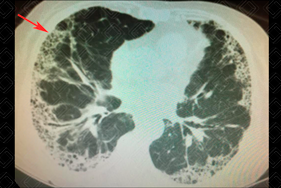

Texto alternativo para a imagem Figuras 1 e 2. Créditos: Dra. Elazir Mota - Rio de Janeiro/RJ

Descrição das figuras 1 e 2: Tomografia computadorizada do tórax, cortes axiais evidenciando opacidades reticulares, vidro fosco e cistos de faveolamento, com predileção periférica, em situação subpleural.

• Tomografia computadorizada do tórax: C aracteriza-se como padrão típico para PIU a presença de opacidades reticulares de predomínio periférico e basal, associado a faveolamento, estando presentes ou não bronquiolectasias de tração (figura 1). Outras manifestações típicas do padrão de pneumonia intersticial usual na TC consistem em linhas intralobulares e espessamento irregular de septos interlobulares, resultando em padrão reticular, distorção arquitetural pulmonar, bronquiectasia, bronquiolectasia de tração e faveolamento.

O que seria faveolamento? Como é feito seu diagnóstico? Critérios para o diagnóstico de faveolamento devem ser aplicados e são definidos como: cistos entre 3-10 mm agrupados, compartilhando paredes e disposição dos cistos em camadas usualmente subpleurais (figura 2).